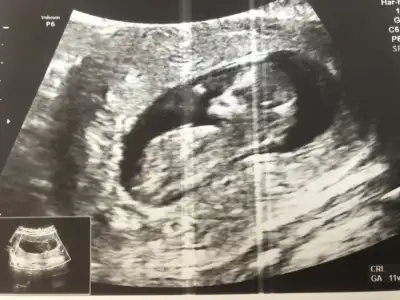

dr soylemeden siz gorun genital nub teorisi ( bebegin cinsiyeti)

Slm geçen hafta usg tahmininde kız demistiniz. Bugün doktorda kız gibi dedi. Pazartesiye fetal dna testini bekliyorum o zaman kesinleşecek 😍